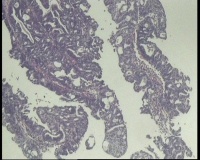

镜下见子宫内膜腺体异型增生,呈乳头状,筛网状排列,细胞核圆形,大小尚均匀,可见少量核分裂像,部分区域鳞化,间质少,部分区域无间质,间质有坏死